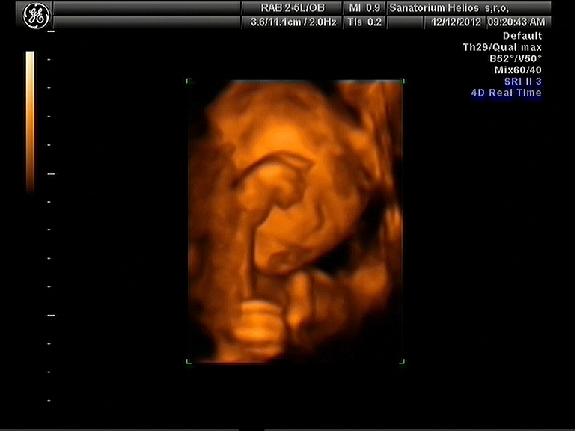

Holky moje to byla pecka

dojdu tam, vysolim love, cekam.. pani doktorka vse nachystala a zacli jsme .. mladej byl zvhuru a mlel se jak blazen a porad rucicky pred oblicejem, ma je tak fakt porad hahaha prej oblibena poloha, kdyz uz tam nemel ruce, tak tam byla placenta takze mlha, nebo pres hlavu mu sel pupecnik haha a kdyz uz holky vypadalo ze fotime, tak zacal strkat pred oblicek nohy

stouchali jsme do nej, ja se prekulovala z bolku na bok

mame par fotek, ale lepsi proste nesli.. video mame i s merenim a srdecnim tepem.. tak Eldinek ma neco malinko pres 500g ..

posilam fota.. jako lepsi proste nebyly hahahah